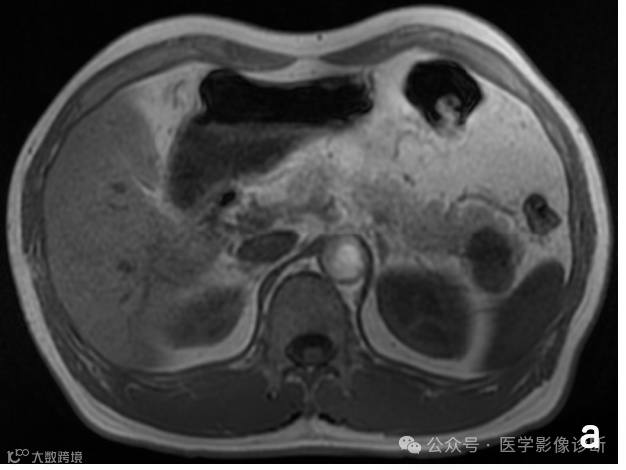

患者,女性,81岁,淋巴瘤化疗后腰痛一周。

腰椎MRI扫描T1WI(A)和T2WI/FS(B)显示多个椎体多发异常信号伴轻度压缩骨折,受恶性肿瘤病史影响放射科医生将其诊断为转移瘤,而遗漏了终版下条带样低信号等良性压缩骨折的征象,患者行椎体活检并成形术后(C),术后病理证实无肿瘤迹象。